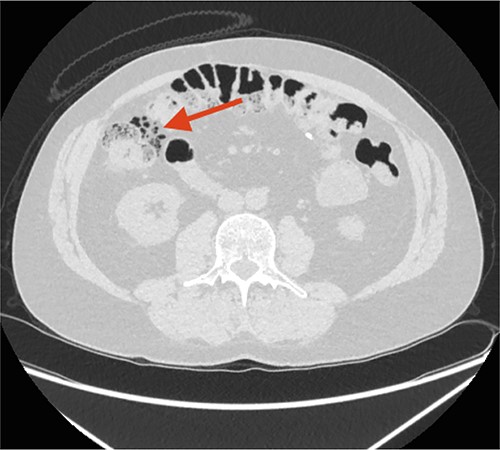

Three weeks later, a CT urography showed FIA, but the patient still had no symptoms indicative of peritonitis. Three months later, a CT scan showed progression of FIA and air bubbles in the wall of the ascending colon (Fig. 3).

CT scan performed 3 months after the first admission to the ED. The arrow points at increased FIA and air bubbles in the colonic wall as signs of Pneumatosis cystoides Intestinalis, PCI.

Pneumatosis cystoides intestinalis (PCI) was suspected.

Retrospectively, the two initial CT scans were reviewed with an independent radiologist, and gas-filled cysts were located in the wall of the ascending colon, representing PCI on both CT scans.